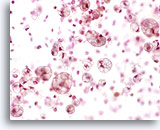

Figure 162

Lipid

The lipid in cases of lipoid pneumonia may be highlighted by oil-red O stain.

Lipid

The lipid in cases of lipoid pneumonia may be highlighted by oil-red O stain.